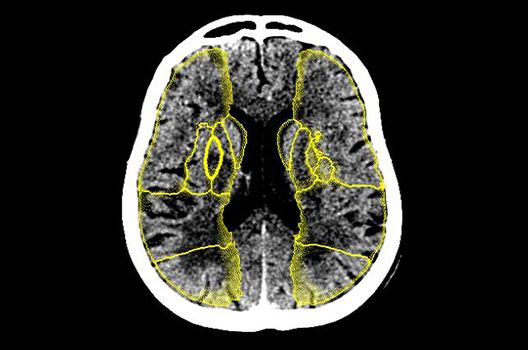

Die Hybridbildgebung mittels PET/MRT spielt insbesondere in der onkologischen Bildgebung eine wichtige Rolle. Eine mögliche Fragestellung ist die Unterscheidung zwischen einem Tumorrezidiv oder therapeutisch assoziierten Veränderungen insbesondere dann, wenn diese Frage mittels MRT alleine nicht beantwortet werden kann.

Die bildgebende Diagnostik und Verlaufsbeurteilung von Tumoren des Nervensystems ist einer der klinischen und Forschungsschwerpunkte unserer Abteilung. Eine besondere Bedeutung kommt der Hybrid-Bildgebung zu. Das Universitätsklinikum verfügt über einen integrierten Ganzkörper-PET/MRT-Scanner, der die Vorteile der MRT-Bildgebung und der Positronenemissionstherapie (PET) vereinigt. Aufgrund der langjährigen klinischen Arbeit und Forschungstätigkeit mit diesem Gerät hat die Neuroradiologie Tübingen maßgeblich zur Etablierung dieses Verfahrens beigetragen. Auch weiterhin forschen wir intensiv an neuen Methoden zur frühen Einordnung von Tumoren und insbesondere Tumorrezidiven, die mit anderen Methoden häufig nicht erfasst werden können.